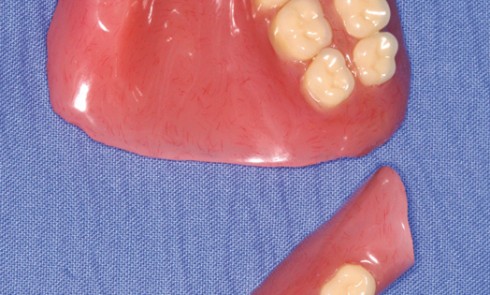

Article réservé à nos abonnés Perte osseuse mandibulaire interruptrice et prothèse amovible implanto-retenue

La mise en œuvre d’une réhabilitation prothétique complète fonctionnelle après chirurgie carcinologique de la mandibule n’est pas toujours aisée, en...